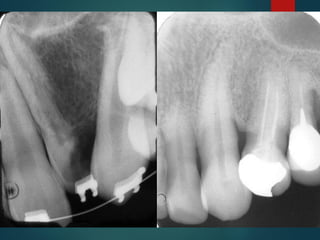

Clasificación Radiográfica

De Las Caries

 Incipiente de esmalte

 De esmalte

 Dentinaria superficial

 Dentinaria profunda

 Sobreproyectada en cámara

pulpar

 Penetrante